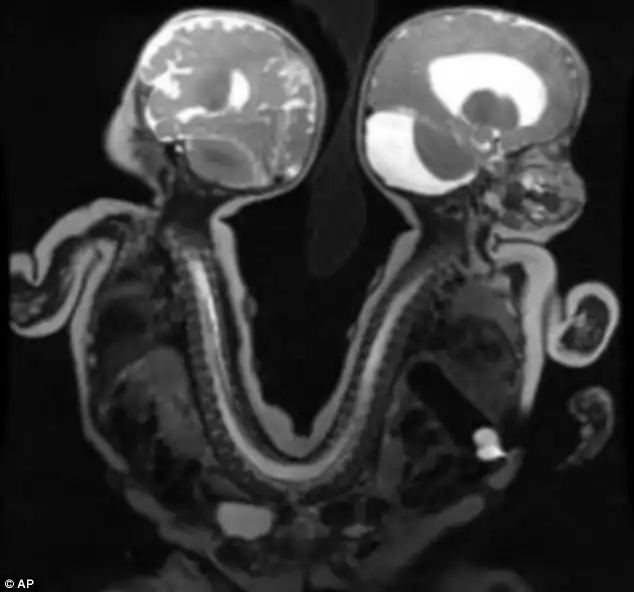

В детской больнице в Мемфисе в американском штате Теннесси хирурги успешно провели уникальную операцию по разделению сиамских близнецов, сросшихся в области крестца.

Темнокожие мальчики Иисус и Иаков родились на свет соединенными спина к спине в области таза и нижней части позвоночника. Часть желудочно -кишечного тракта у них тоже была общей. В остальном же они были полностью функциональны и здоровы.

Провели сложную 13-часовую операцию еще 29 августа и на данный момент разделенные дети чувствуют себя очень хорошо и впервые могут увидеть друг друга в лицо.